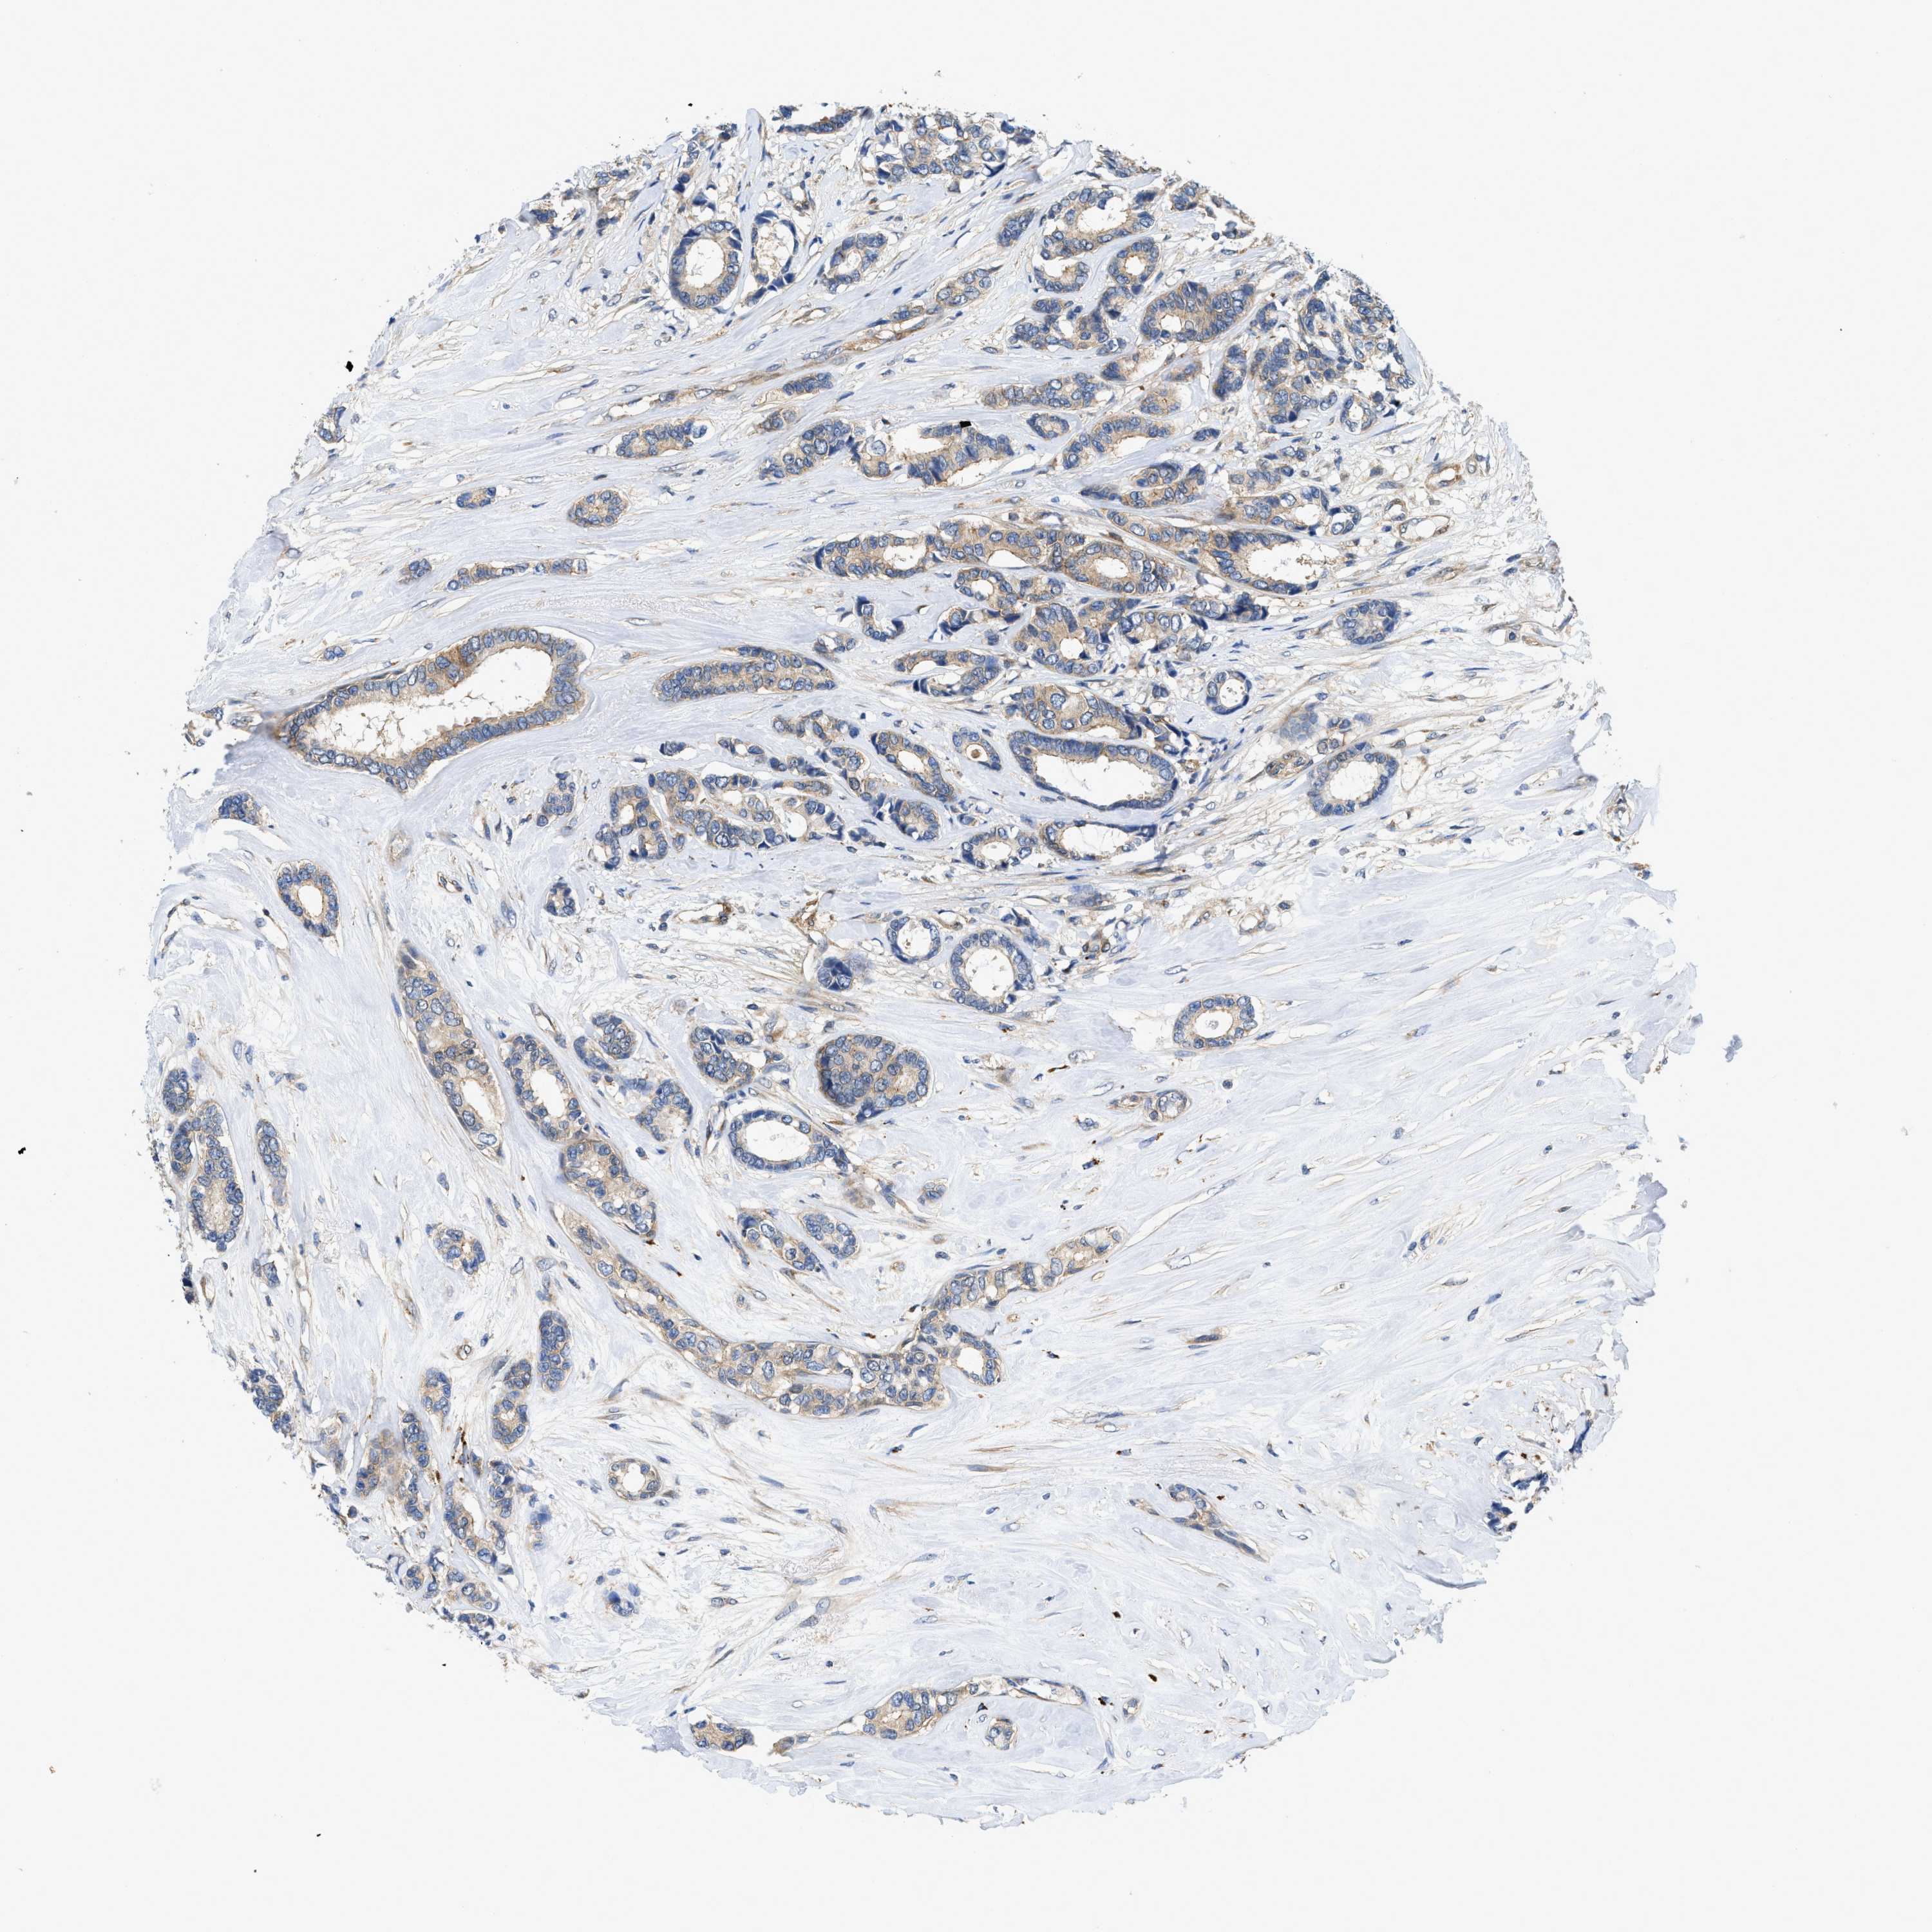

CANCER BREAST CANCER Show tissue menu

BRCA TCGA BRCA VALIDATION PROTEIN EXPRESSION